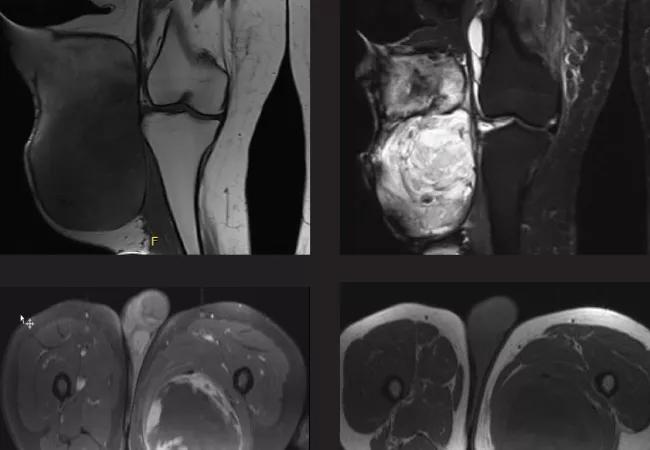

Figure 1. Coronal T1 (top left) and STIR (top right) imaging show a complex, cystic mass with a high degree of heterogeneity on STIR imaging, more homogeneous in appearance on T1 (this can be typical of “hematomas”). The mass is adjacent to the medial knee joint capsule but does not violate the knee joint. Axial T1 (bottom left) and fat saturation [FS] (bottom right) imaging show a large mass that is adjacent to the medial knee tissues, surrounded by a dark rind on T1/FS sequences. This was thought to represent a “spontaneous hematoma,” but was proven to be a high-grade soft tissue sarcoma following open biopsy. It was later resected and the defect covered with a lateral gastrocnemius flap.